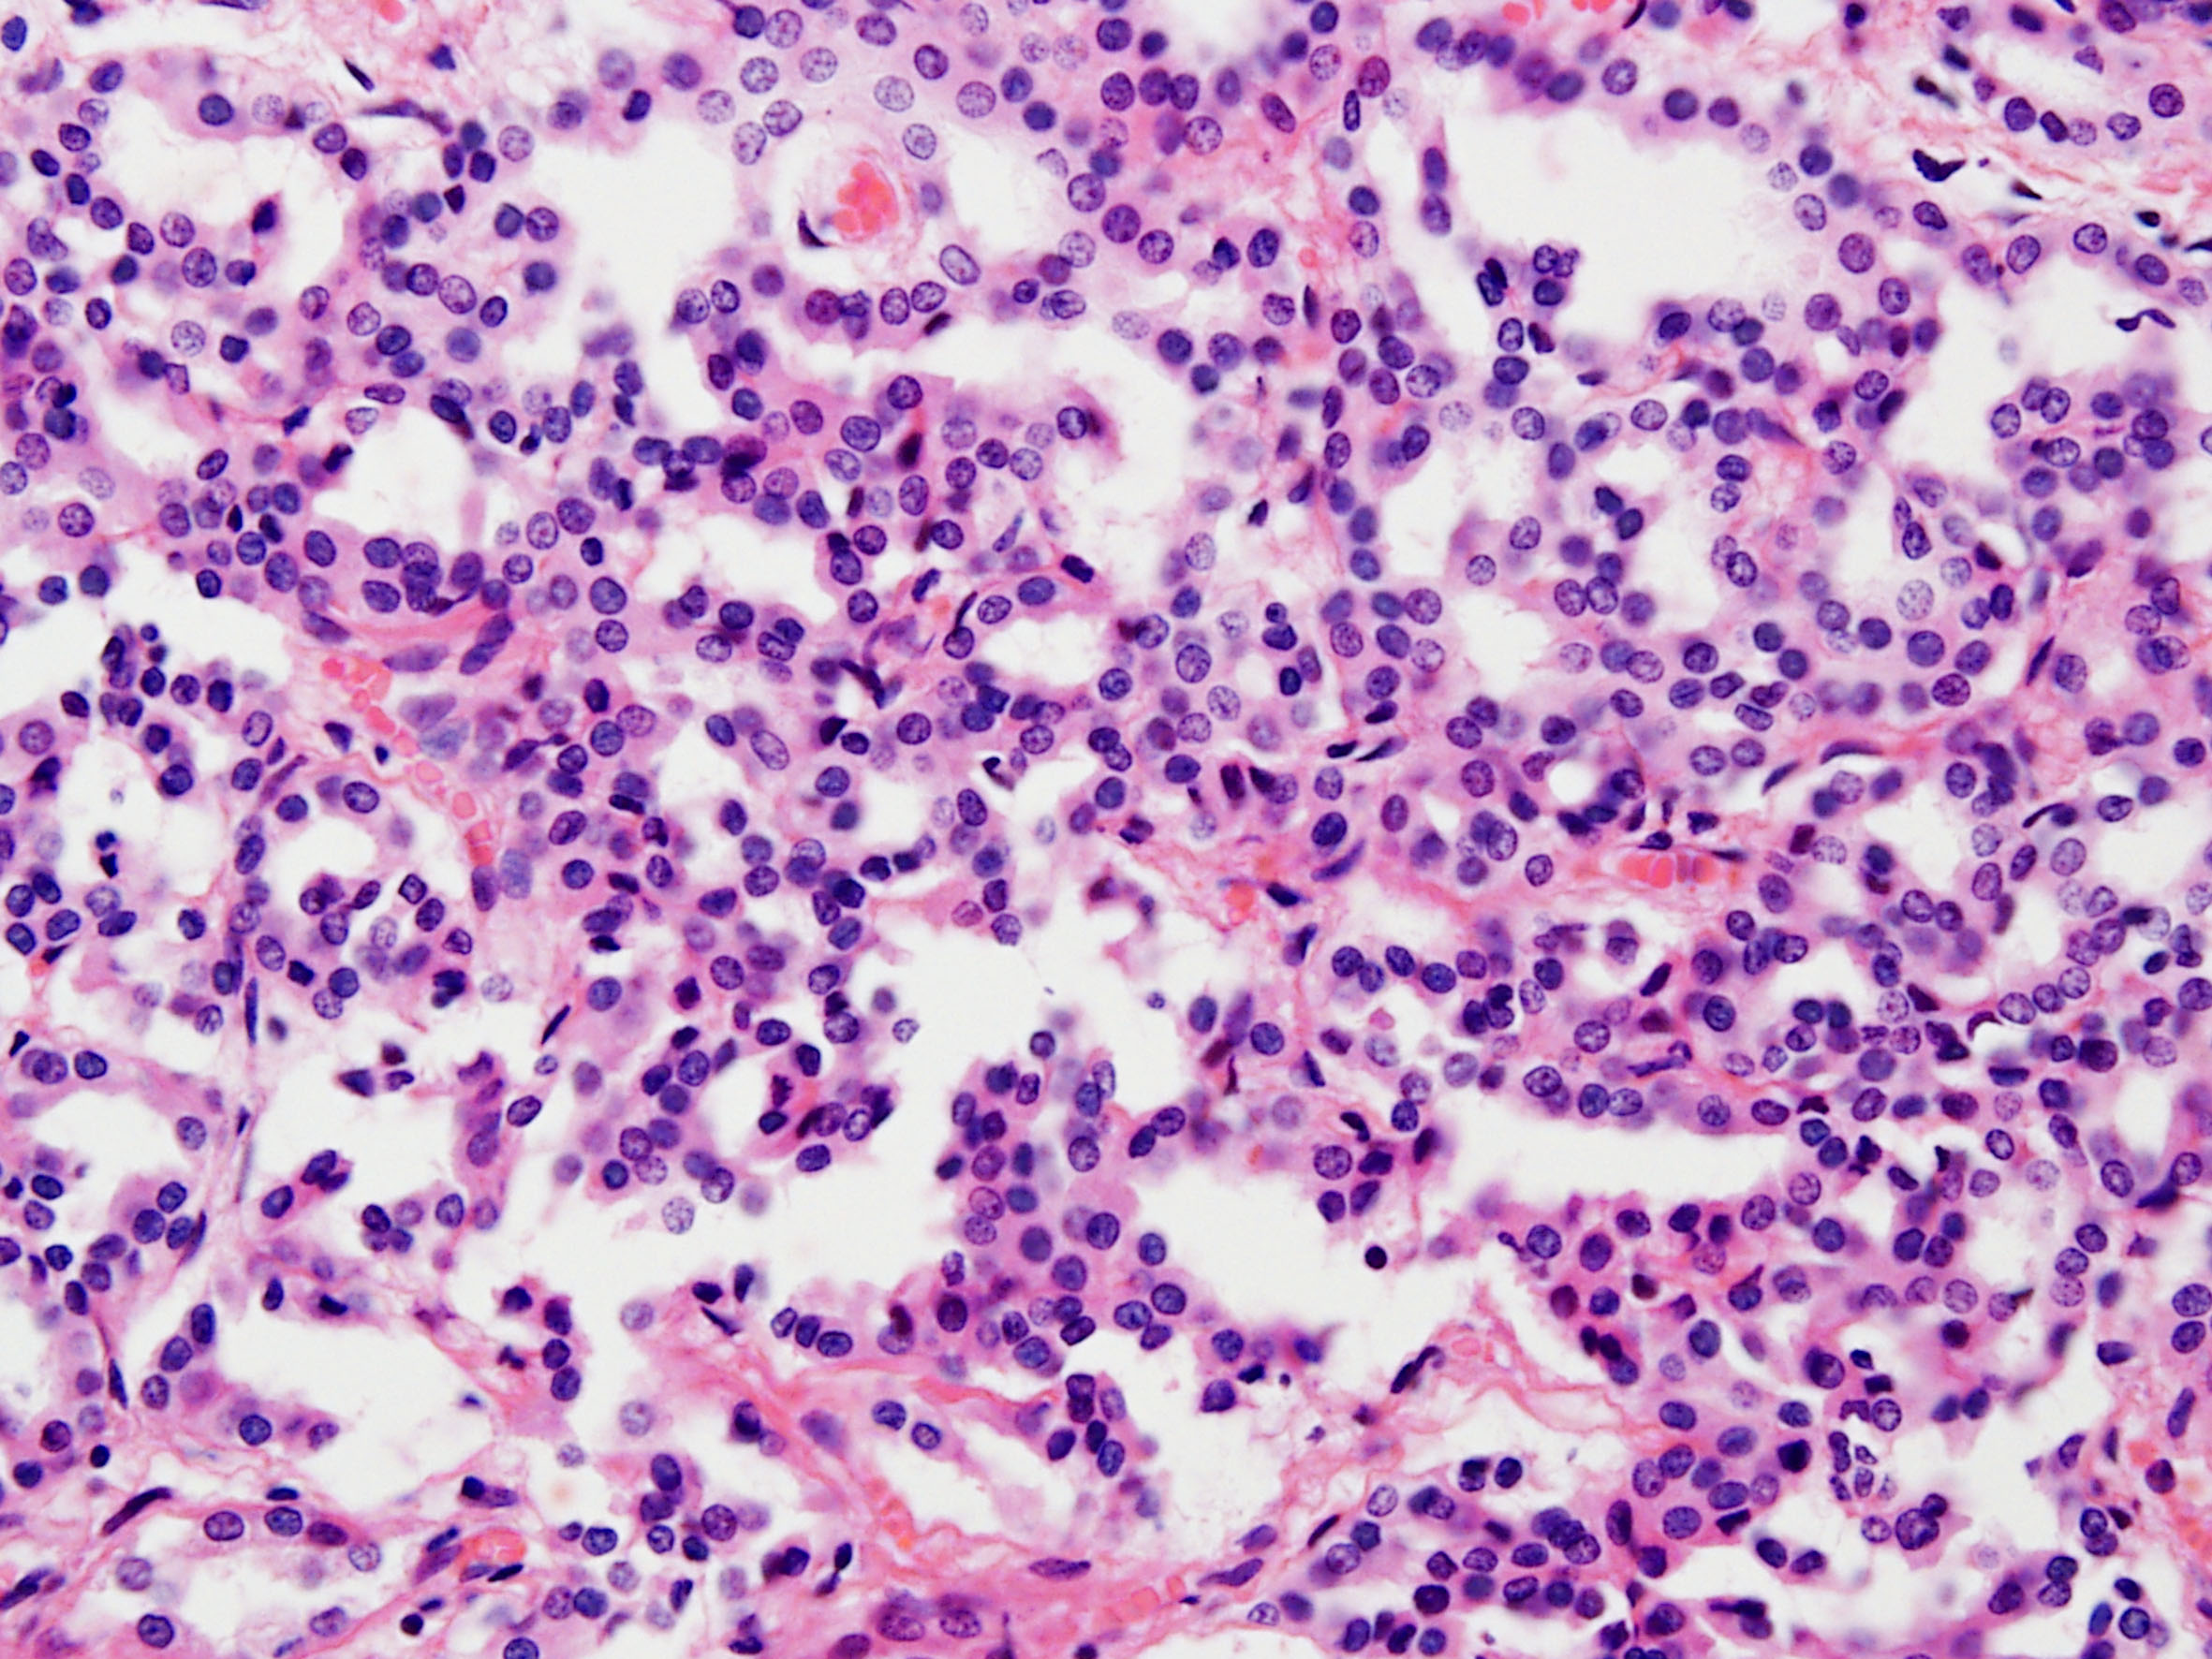

Classification of renal tumors

Case ID: 228